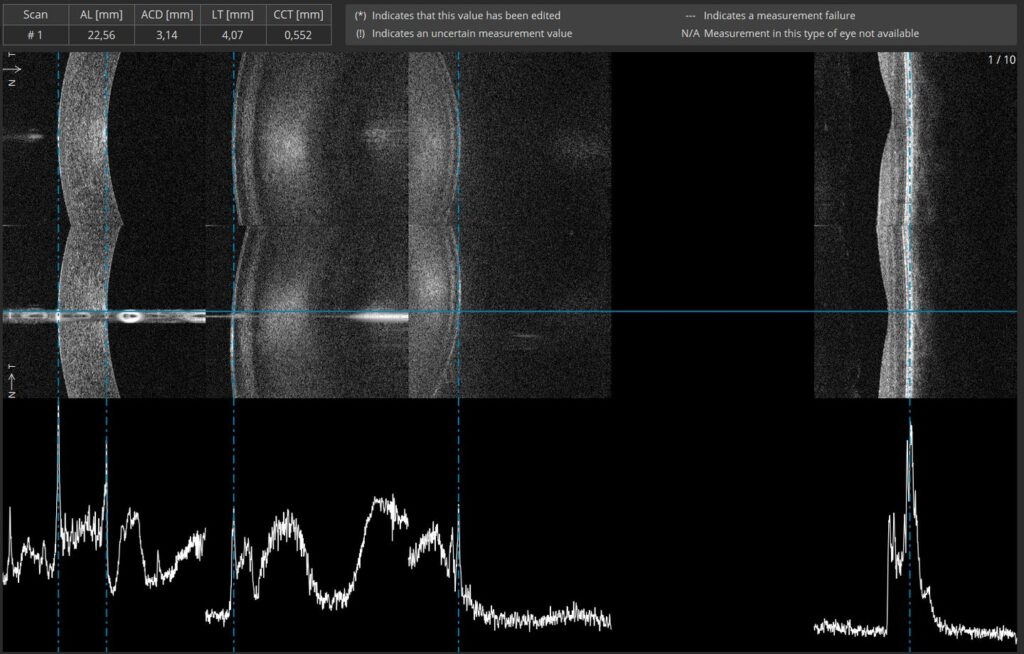

B-OCT® Innovative method of using the posterior OCT device to measure ocular structure along eye axis. OCT Biometry provides a complete set of Biometry parameters: Axial Length (AL), Central Cornea Thickness (CCT), Anterior Chamber Depth (ACD), Lens Thickness (LT), White to White (WTW), Pupil (P).

B-OCT® enables measurement of ocular axial dimensions using a conventional OCT system. During the examination, the scanning light beam passes through ocular structures located along the visual axis and the following are identified: the anterior and posterior boundary of the cornea, the anterior and posterior boundary of the lens, as well as the posterior boundary of the retina.

Verify your measurement visually

The biometry image provided by the REVO FC presents measurement calipers on all structural boundaries of the eye. This enables easy visual identification of the measured structures or manual correction of the measurement. With a simple cursor shift, it is possible to precisely set boundaries in difficult cases with 5 μm axial resolution. The device eliminates the common uncertainty of how the optical biometer classifies the boundaries in non-typical patients.

• 3 mm scan enables precise evaluation of the Retina condition,

• 5 μm resolution gives the highest level of details.